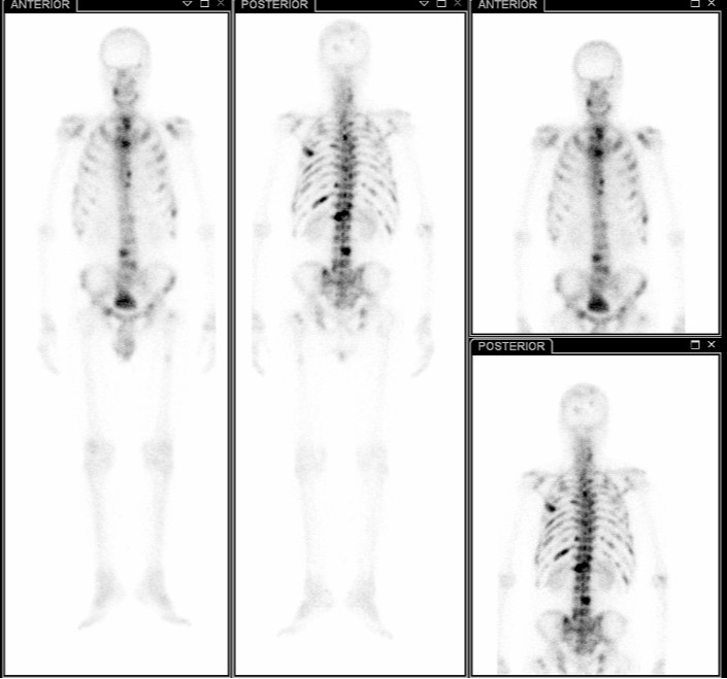

骨扫描检查(2024-10-15)

图片3.png

全身骨显像清晰,颅骨多处、脊柱多处、左右两侧肋骨多处、骨盆多处及四肢骨多处均可见多发异常放射性浓聚。